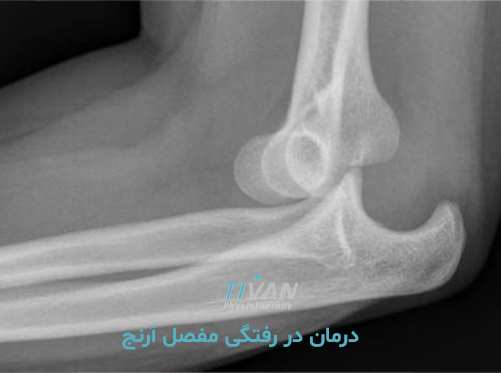

درمان در رفتگی مفصل آرنج یکی از مهمترین اقدامات پس از آسیبهای ناگهانی در ناحیه آرنج است که میتواند عملکرد حرکتی دست را به حالت طبیعی بازگرداند. مفصل آرنج یکی از پیچیدهترین مفاصل بدن است که نقش مهمی در حرکات روزمره مانند بلند کردن اجسام، نوشتن، کار با رایانه و حتی غذا خوردن دارد. دررفتگی این مفصل میتواند تأثیرات جدی بر کیفیت زندگی فرد داشته باشد، بهویژه اگر بهموقع درمان نشود. دررفتگی مفصل آرنج اغلب در اثر زمین خوردن، ضربه مستقیم یا حرکات ناگهانی بازو اتفاق میافتد و موجب جابجایی استخوانهای ساعد نسبت به استخوان بازو میشود. این جابجایی دردناک ممکن است با آسیب به رباطها، تاندونها یا اعصاب همراه باشد.

در اغلب موارد، دررفتگی آرنج با جااندازی و فیزیوتراپی قابل درمان است. جراحی تنها در موارد پیچیده مانند آسیبهای همزمان به اعصاب یا شکستگیهای همراه توصیه میشود.